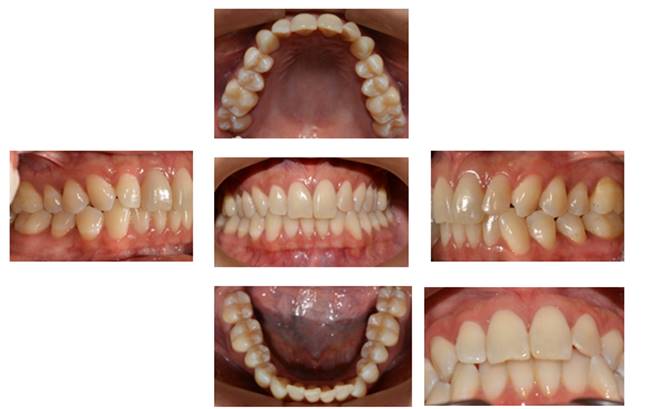

Methods: The clinical examination included extra-oral and intra-oral photographs, panoramic radiographic, lateral cephalometric, stone casts, and upper and lower arch analysis obtained from ClinCheck 3.0.The treatment planning was resolved the crowding in both upper and lower arches and the severe rotation of 33 tooth (46°) using Invisalign system as well as the canine and molar relationship, dental verticalization, adequate over jet, overbite and dental midline using the same system. The duration of the treatment was approximately eight months.

Results: In Post-treatment extra oralphotographs, no significant changes were observed at the end of the treatment. Intraoral photographs showed an important and notable improved aesthetics. The canine relationship improved slightly and molar Class Irelationship was maintained. An increase in transverse diameter was observed at the level of first premolars, second premolars and first molars. The overbite was improved. The crowding and the severe canine rotation were corrected. No obvious root resorption was radiographically evident and slight cephalometric changes.